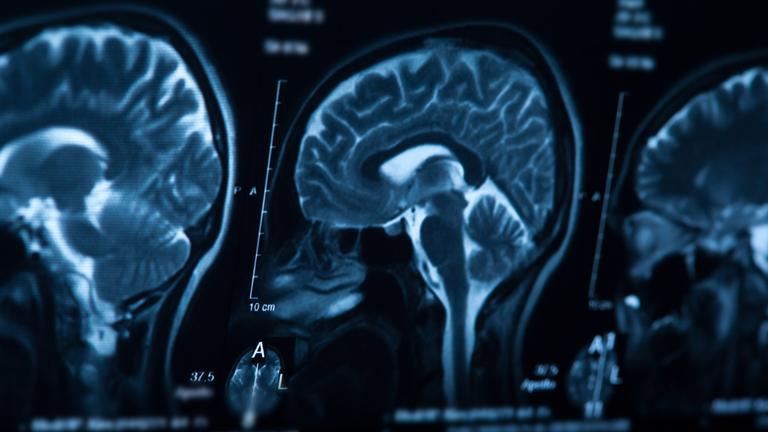

14. Röntgenaufnahme eines Gehirns

1. CT-Bilder von einem Gehirn